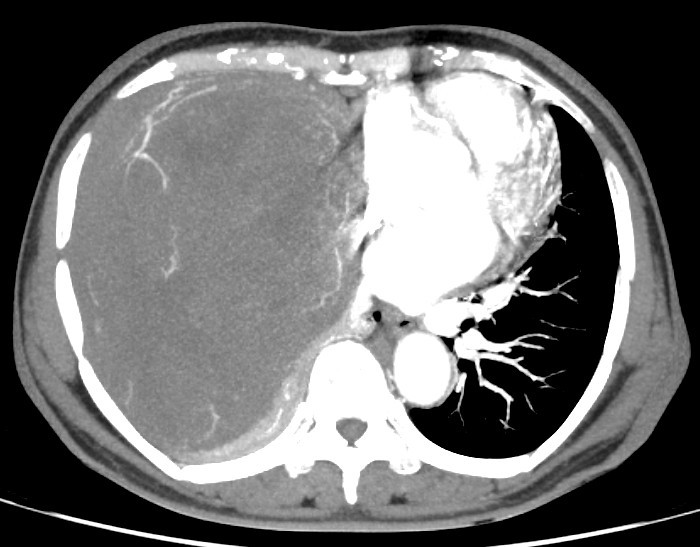

Kết quả chụp cắt lớp vi tính tại bệnh viện Ung Bướu Hà Nội cho thấy, lồng ngực phải có khối đặc kích thước 20x15 cm đè xẹp phổi, thâm nhiễm trung thất, thành ngực. Bệnh nhân được tiến hành sinh thiết khối u, kết quả giải phẫu bệnh là u xơ đơn độc.

| Hình ảnh khối u choán hết khoang lồng ngực của bệnh nhân - Ảnh BVCC |

TS.BS. Phan Lê Thắng, Trưởng khoa Ngoại Theo yêu cầu, Bệnh viện Ung Bướu Hà Nội cho biết, ekip phẫu thuật đã phải hội chẩn tính toán kĩ trước mổ vì các thao tác phẫu thuật phải thực hiện trong trường mổ vô cùng chật hẹp. Khối u giàu mạch nuôi nên phẫu thuật viên phải phẫu tích tỉ mỉ, tìm và khống chế nguồn nuôi để đảm bảo an toàn cuộc mổ và hạn chế mất máu cho bệnh nhân.